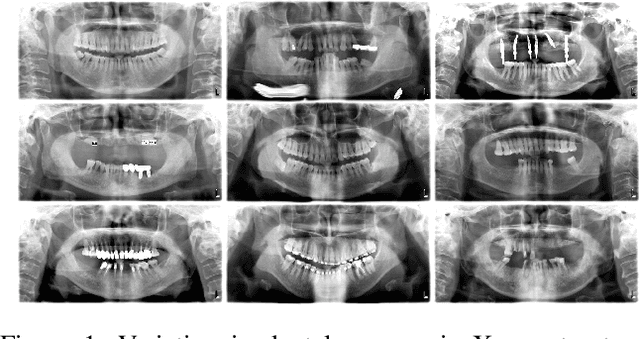

Abstract:Accurate identification and segmentation of dental caries in panoramic radiographs are critical for early diagnosis and effective treatment planning. Automated segmentation remains challenging due to low lesion contrast, morphological variability, and limited annotated data. In this study, we present the first comprehensive benchmarking of convolutional neural networks, vision transformers and state-space mamba architectures for automated dental caries segmentation on panoramic radiographs through a DC1000 dataset. Twelve state-of-the-art architectures, including VMUnet, MambaUNet, VMUNetv2, RMAMamba-S, TransNetR, PVTFormer, DoubleU-Net, and ResUNet++, were trained under identical configurations. Results reveal that, contrary to the growing trend toward complex attention based architectures, the CNN-based DoubleU-Net achieved the highest dice coefficient of 0.7345, mIoU of 0.5978, and precision of 0.8145, outperforming all transformer and Mamba variants. In the study, the top 3 results across all performance metrics were achieved by CNN-based architectures. Here, Mamba and transformer-based methods, despite their theoretical advantage in global context modeling, underperformed due to limited data and weaker spatial priors. These findings underscore the importance of architecture-task alignment in domain-specific medical image segmentation more than model complexity. Our code is available at: https://github.com/JunZengz/dental-caries-segmentation.